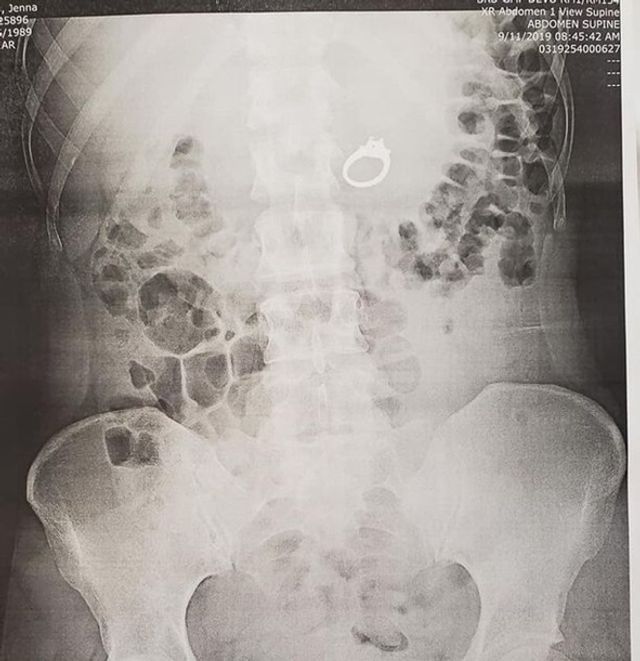

Мешканка США проковтнула золотий перстень з великим діамантом через те, що їй наснилися грабіжники.

Дівчина Дженна Еванс з Каліфорнії побачила уві сні, як за нею біжать грабіжники. Американка сховала обручку в роті, щоб її не вкрали.

Коли 29-річна дівчина прокинулася, то не виявила прикраси на пальці і запідозрила, що дійсно уві сні сховала її в роті. Еванс розбудила свого коханого і розповіла йому про те, що трапилося. Чоловік довго не міг повірити в історію своєї дівчини, але погодився відвезти її в лікарню.

За допомогою рентгенівського знімка лікарі виявили перстень, який опинився вже в шлунку дівчини. Прикрасу дістали за допомогою ендоскопа. Сама Дженна каже, що після того, як перстень дістали, його віддали чоловіку, а не їй. Хлопець вручить Дженні обручку, переконавшись, що їй більше не сняться такі страшні сни.